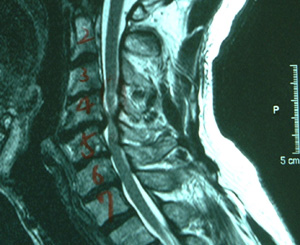

| 水平断面 (頸椎第5番/6番) |

![]() |

| 所見 | 脊柱管が狭く、脊髄は圧迫されブーメラン状に変形している。 | 脊髄は本来の姿である楕円形状に戻り、除圧されていることがわかる。 |